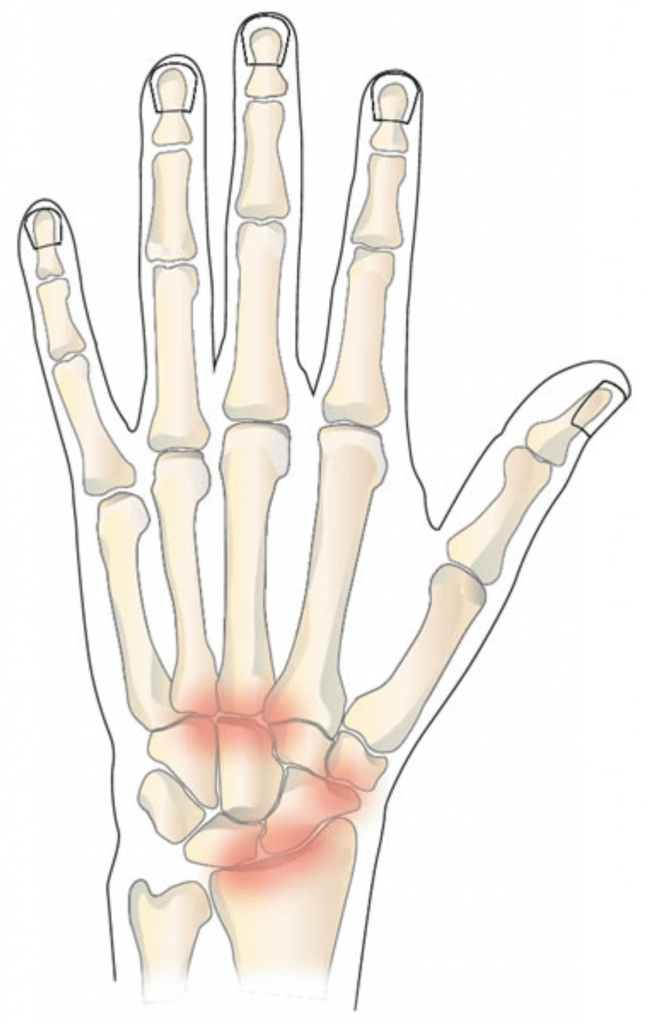

3. Artritis

El término artritis hace referencia a la inflamación de las articulaciones. Esta afección suele cursar con dolor y rigidez.

En el caso de la muñeca, el origen de la artritis puede ser muy variado, desde traumático hasta inflamatorio o relacionado con enfermedades reumáticas.

4. Esguinces de Muñeca

Un esguince de muñeca se produce cuando uno (o varios) ligamentos que dan estabilidad a las articulaciones de la muñeca, se estiran más allá de sus límites fisiológicos. Al producirse este movimiento, pueden producirse lesiones que van desde una distensión o una pequeño desgarro de los ligamentos, hasta una rotura parcial o total de los mismos. Es importante acudir al médico para recibir un diagnóstico diferencial y conocer el alcance de la lesión.